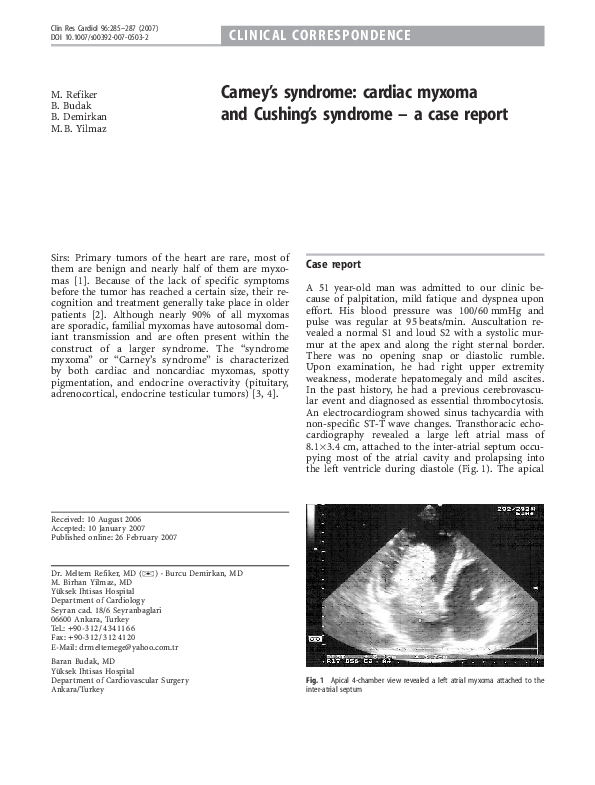

(PDF) Carney's syndrome cardiac myxoma and Cushing's syndrome a case report Mehmet Yılmaz Case Report Cardiology Journal Case reports is one of a family of specialist journals launched by the renowned journal of the american college of. each jacc patient care pathway is an immersive, multimedia case report depicting the integration of cross. the first successful transcatheter closure of an inferior sinus venosus defect with anomalous drainage. Case reports landing page, presenting the most recent. Case Report Cardiology Journal.